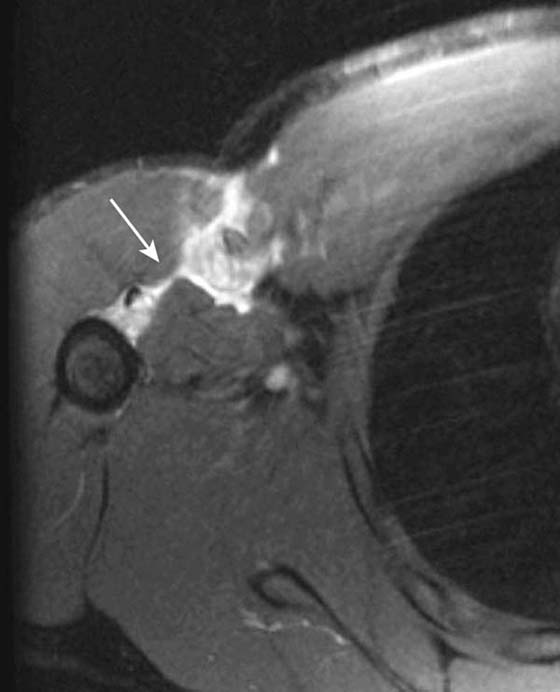

Radiography is useful in defining osseous alignment at the glenohumeral joint and may demonstrate a Hill–Sachs or bony Bankart’s lesion. CT also has utility in the assessment of osseous structures after subluxation/dislocation, particularly in evaluation of a subtle Bankart’s fracture with an equivocal MRI or intra-articular osseous fragments.21 CT is useful as a preoperative exam to assess fragment size and displacement. MR arthrography is the most sensitive test for evaluation of most of the causes, manifestations, and sequellae of glenohumeral instability.22-24 It allows for precise evaluation of the capsulolabral and ligamentous complex. Labral tears are diagnosed when intra-articular contrast material tracks into or underneath the labrum. Noncontrast MRI is also very sensitive, although use of a high-field scanner (≥0.7 T) is recommended. Labral tears most commonly associated with instability are anteroinferior or posterior (Fig. 14-9). Superior labral tears that track anterior to posterior (SLAP tears) are well seen with MR arthrography but are not usually associated with instability25,26 (Fig. 14-10). Tendon tears that can be associated with instability, including tears of the long head of the biceps tendon or subscapularis, are also well seen by MR arthrography and noncontrast MRI. Multidirectional instability typically shows no abnormality on imaging modalities, although capacious recesses may be observed.

Figure 14-9 Bankart’s and Hill–Sachs lesions. Axial T1 fat-saturated MRI after administration of intra-articular gadolinium (direct MR arthrogram) demonstrates sequelae of anterior shoulder dislocation. The anteroinferior labrum and bony glenoid has been disrupted (white arrow) consistent with a bony Bankart lesion. A bony defect is also seen at the posterior humeral head (curved black arrow) consistent with a Hill–Sachs lesion.